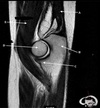

Q

ANTERIOR LABRUM

Not at all

4

12

A

1

3

Perfectly

What is letter C?

How well did you know this?

2

5

POSTERIOR LABRUM